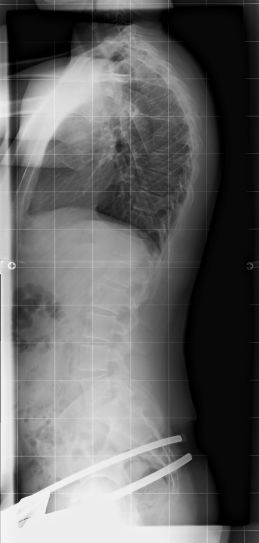

Uuuuuuuuuuuuuuund jetzt das wichtigste: Röntgen ohne Korsett 61° ( wurde vor paar Wochen nochmal geröntgt, da die letzte Aufnahme zu lange zurücklag)

Röntgen mit Korsett: 31 ° :) :) :) :) :) :)

hier nun endlich die röntgenbilder

Dateianhänge

kyphose1.jpg

kyphose1.jpg (15.96 KiB) 16672 mal betrachtet

kyphose2.jpg

kyphose2.jpg (14.01 KiB) 16672 mal betrachtet